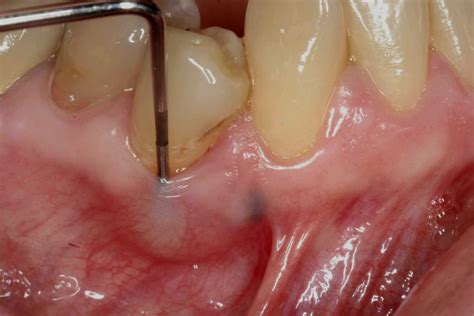

The Development of Pockets

As the infection deepens, your body’s immune system attempts to fight the bacteria, leading to the creation of pus. This fluid accumulation creates immense pressure, which is why the pain becomes intense and throbbing. You might notice a small, pimple-like bump on your gums near the affected tooth, known as a fistula. This is an exit point for the infection.

During your visit, the dentist will likely perform an X-ray to determine the extent of the infection and its location. Treatment may involve a root canal to save the tooth, an incision and drainage procedure to release the pus, or, in severe cases, tooth extraction. Your dentist may also prescribe antibiotics to manage the infection, though this does not replace the need for physical intervention.